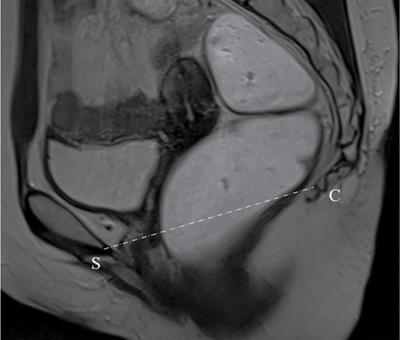

PELVIC FLOOR IMAGING – ANTERIOR AND MIDDLE COMPARTMENTS Anu Epean, Deepa Korula The term ‘Pelvic floor disorder’ refers to dysfunction of the pelvic floor musculature and connective tissues which provide support for the pelvic organs. This can produce a wide range of symptoms such a urinary incontinence, straining to void, dyspareunia, constipation, faecal incontinence and organ prolapse. The greatest risk factors for pelvic floor disorders are female sex and advanced age. Other risk factors include obesity, pregnancy, multiparity, smoking, connective tissue disorders. The pelvic floor is broadly divided into three compartments. The bladder and urethra form the anterior compartment. The vagina and uterus form the middle compartment and the posterior compartment comprises of the rectum and anal canal (Fig. 7.16.1.1). The attachment of the fascia, muscles and the ligaments to the bony pelvis form the support for these structures. From cranial to caudal, there are three layers which make up the pelvic floor – the endopelvic fascia, the pelvic diaphragm and urogenital diaphragm. This is the most cranial layer of pelvic floor, lying deep to peritoneum. It is a fine structure, comprising of a network of connective tissue which encases the pelvic viscera, provides support to the pelvic organs and maintains their anatomic relationship. There are several condensations of this fascia and ligaments which provide support in each of the pelvic compartments. In the anterior compartment, a fascial condensation called pubocervical fascia extends from anterior vaginal wall to the pubis. Tear in the pubocervical fascia can cause cystocele and urinary incontinence. There are three groups of ligaments which provide urethral support – periurethral, paraurethral and pubourethral ligaments. The periurethral ligaments arise from medial fibres of pubococcygeus and pass ventral to urethra. The paraurethral ligaments connect the lateral wall of urethra to periurethral ligament and pubourethral ligament connects the lateral wall of urethra to arcus tendineus. The urethra lies on a Hammock-like supportive layer of endopelvic fascia and anterior vaginal wall, which are stabilized by attachment laterally to arcus tendineus and levator ani (Fig. 7.16.1.2). In the middle compartment, condensations of the endopelvic fascia which attach the uterus to the lateral pelvic wall is called parametrium, which is made up of the uterosacral and cardinal ligaments. The uterosacral cardinal ligament complex supports and suspends the cervix and upper vagina above the levator plate. More inferiorly, the paracolpium attaches the vagina to the lateral pelvic wall. There are three levels of fascial support to the vagina: In the posterior compartment, the perineal body located within the rectovaginal septum supports ligaments and muscles and prevents abnormal widening of levator hiatus (Fig. 7.16.1.3). The rectovaginal fascia extends from posterior wall of vagina to anterior rectal wall. A tear in the rectovaginal fascia is the cause for an anterior rectocele. Arcus tendineus levator ani (ATLA) is formed by the condensation of the endopelvic fascia laterally, along the pelvic sidewall. This extends obliquely from inferior pubic symphysis to ischial spine and provides lateral support to the pelvic organs and attachment of the levator ani. Fascial condensations are not visualized on imaging; however, organ prolapse, due to deficiency in any of these, can be detected on MRI. The levator ani and the coccygeus muscles make up the pelvic diaphragm. The levator ani is the primary muscle of the pelvic diaphragm and is attached to the pubis and to the ATLA laterally on both sides. The slow twitch fibres of the levator ani continuously contract, maintaining tone to the pelvic floor and suspending the pelvic organs in the correct position. The two most important components of the levator ani are the iliococcygeus and puborectalis muscles. The iliococcygeus arises from external anal sphincter and has a curved shape, concave inferiorly. It fans out laterally to its insertion in the posterior part of arcus tendineus (Fig. 7.16.1.4A and B). Posteriorly, in the midline, condensations of ilococcygeus form a firm raphe anterior to coccyx called the anococcygeal ligament or levator plate. The pubococcygeus muscle is a component of the levator ani. It forms the anteromedial part and is a thick bundle of fibres arising from the pubis and anterior portion of arcus tendineus. It extends horizontally back to behind the rectum, medially forming the margin of urogenital hiatus (Fig. 7.16.1.5A). The anorectal and urogenital hiatus are closed by the contraction of the pubococcygeus muscle. This enables support during rest and in situations where the intraabdominal pressure is increased. The medial fibres of pubococcygeus, depending on their attachment to urethra, vagina, anus and rectum are termed as pubourethralis, pubovaginalis, puboanalis and puborectalis, collectively as pubovisceralis. The puborectalis forms a sling around the rectum (Fig. 7.16.1.5B). The muscles of the pelvic diaphragm are well delineated on MRI. The urogenital diaphragm or perineal membrane is the most caudal layer of the pelvic floor. It has a triangular appearance, extending from the pubic symphysis and the ischiopubic ramus to the posterior perineal body. It is ventral to the external anal sphincter and perineal body. It is attached to the surrounding structures such as the perineal body, external anal sphincter, vagina and the bulbocavernosus muscle. Imaging has an increasing role in the evaluation of pelvic floor disorders. Clinical examination alone has a low sensitivity and specificity for the detection of multicompartment involvement and organ prolapse. Imaging helps to detect involvement of multiple pelvic compartments and thus to plan surgery. Ultrasound, MRI and conventional imaging which includes voiding cystourethrography, evacuation proctography and dynamic cystocolpoproctography (DCP) are used to evaluate the pelvic floor. It is easily available, cheap and does not involve ionizing radiation. In the evaluation of the anterior compartment, ultrasound is more reliable than MRI. Transperineal ultrasound using 2D, 3D or 4D techniques along with dynamic imaging helps to evaluate pelvic floor dysfunction. Patient is placed in a dorsal lithotomy position for a transperineal scan although a standing position can also be used. Convex transducer (2–6 MHz) or endoluminal transducers (endovaginal/endorectal) maybe used. In a midsagittal translabial scan, the anatomic relationship of urethra, bladder, vagina, cervix and anorectum can be studied and the relative position of these organs determined by use of certain measurements. The bladder-symphysis distance (BND) is the distance between the bladder neck and lowest margin of symphysis pubis and demarcates position of the bladder neck. Measurement of BND is made at rest and during Valsalva manoeuvre and the difference in BND between the two, gives the measure of bladder neck descent. There are no definite values to indicate normal descent but there is a proposed cut off of 20, 25, 30 mm to indicate hypermobility (Fig. 7.16.1.6A and B). The proximal urethra rotates posteroinferiorly during Valsalva manoeuvre and this can be measured by the posterior urethrovesical angle (β) or the gamma angle. The posterior urethrovesical or retrovesical angle (β) is the angle between a line through the urethral axis and the line through the trigonal surface of the bladder and varies from 90–120 degrees normally. This may increase to 160–180 degrees and can be associated with funnelling of bladder neck. The gamma angle is the angle between a line through the inferior margin of pubic symphysis and the urethrovesical junction. This is seen on Valsalva manoeuvre or at rest in patients with stress incontinence (Fig. 7.16.1.7). Color Doppler can demonstrate urine leakage on performance of Valsalva or at rest. Other abnormalities that can be detected on transperineal ultrasound are cystocele, urethral diverticulum, Gartner duct cyst, foreign body or bladder tumour. 3D pelvic ultrasound is useful to evaluate pelvic floor dysfunction and to study the urethra, levator ani complex, paravaginal supports, prolapse and implant imaging. 4D ultrasound helps in real-time, dynamic imaging of pelvic floor. In the middle compartment, although uterine prolapse is often clinically evident, it can also be detected by ultrasound. Uterine prolapse can be also quantified by measuring maximum descent of uterus from the reference point which is the inferior margin of pubic symphysis. Ultrasound is also useful to evaluate for surgical planning in a large retroverted uterus with an anteriorly placed cervix causing voiding symptoms. MRI is useful in the evaluation of pelvic floor as it provides good anatomic detail about the pelvic floor muscles, ligaments because of its inherent superior soft tissue resolution. In addition, dynamic MRI yields functional information. MRI defecography is a dynamic study performed to study the posterior pelvic compartment but it also gives information about the anterior and middle compartments. It can be performed both with closed magnet and open magnet systems. The patient is positioned supine with phased array coil around pelvis in a closed magnet system. In an open magnet system, the patient is in a sitting and more physiological position; however, due to the lower signal to noise ratio and lower resolution, a closed magnet system is preferred. Bowel preparation with use of laxative on night before the scan is optional. Voiding prior to the study is encouraged since an overdistended bladder can cause misinterpretation of results. Presence of some urine in the bladder is however, helpful to detect anterior vaginal prolapse. Instructions are given to the patient, prior to the procedure, about the ‘rest’, ‘squeeze’, ‘strain’ and ‘defecate’ phases of dynamic imaging, to ensure that movement or lifting of the pelvis does not occur during these manoeuvres. The rectum is filled with up to 200 mL of ultrasound gel. The patient is made to wear an adult diaper and covered with an incontinence pad on the gantry. Vaginal gel, ∼50 mL maybe introduced since this helps to delineate anatomic landmarks and detect uterovaginal prolapse. Initial large FOV T1 localizer scans help to identify the midline sagittal section of pelvis. T2-weighted fast spin echo, high-resolution sequences in sagittal, axial, coronal planes are used to obtain anatomic detail. This is followed by dynamic imaging of the pelvic floor with use of steady state imaging sequences such as True fast imaging with steady state precession (TrueFISP Siemens) and balanced fast field echo (balanced FFE Philips). Steady state sequences have the advantage of short acquisition times and higher signal to noise ratio and hence useful to obtain rapid serial midsagittal images while patient performs ‘squeeze’, ‘strain’ and ‘defecates’. There are several points and lines for measuring and staging pelvic organ prolapse on MRI; however, the PCL line is said to have the highest interobserver and intraobserver reliability of MRI measurements compared to all proposed reference lines and is described below: Pubococcygeal line (PCL): defined as the line that connects the inferior portion of the pubic symphysis to the last coccygeal joint. The PCL is the most commonly used reference line for the assessment of pelvic floor disorders (Fig. 7.16.1.8).